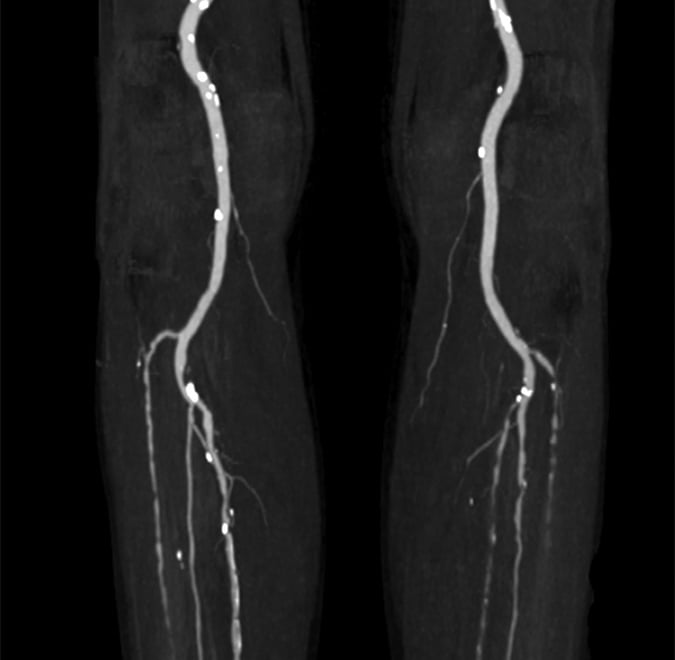

Leg Circulation& Peripheral Artery Treatments

Poor circulation in your legs can signal heart disease. Through peripheral angioplasty, limb salvage procedures, and endovascular therapies, Dr. Anil restores blood flow, prevents amputation, and improves mobility and quality of life.